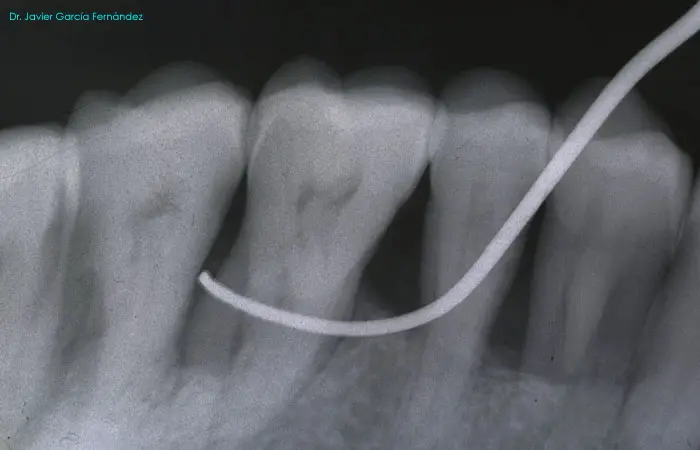

Atlas of Surgical Techniques in Periodontics. Chapter I. Diagnostic of Peridontal Diseases. Classification. Atlas de Técnicas Quirúrgicas en Periodoncia. Cap. I. Exploración y Diagnóstico. Atlas de Técnicas Quirúrgicas en Periodoncia